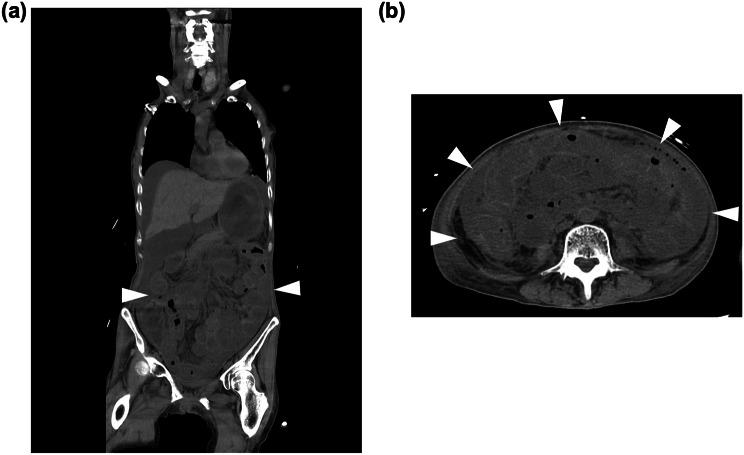

研究期间,147 例患者接受了含伊立替康的化疗。3 例患者在伊立替康治疗后因中性粒细胞减少性肠炎并发感染性休克,144 例患者未发生感染性休克。3 例感染性休克患者均为复发性宫颈癌,均携带 UGT1A1 基因杂合变异(2 例为*1/6,1 例为1/*28 变异),有同期放化疗史、50-60 Gy 盆腔放疗和铂类联合化疗史。盆腔放疗史被认为是含伊立替康化疗后发生感染性休克的可能危险因素(OR 63.0,95%CI 5.71-8635;p<0.001)。在完全病例分析中,UGT1A1 多态性与感染性休克的 OR 为 9.09(95%CI 0.86-1233;p=0.070)。